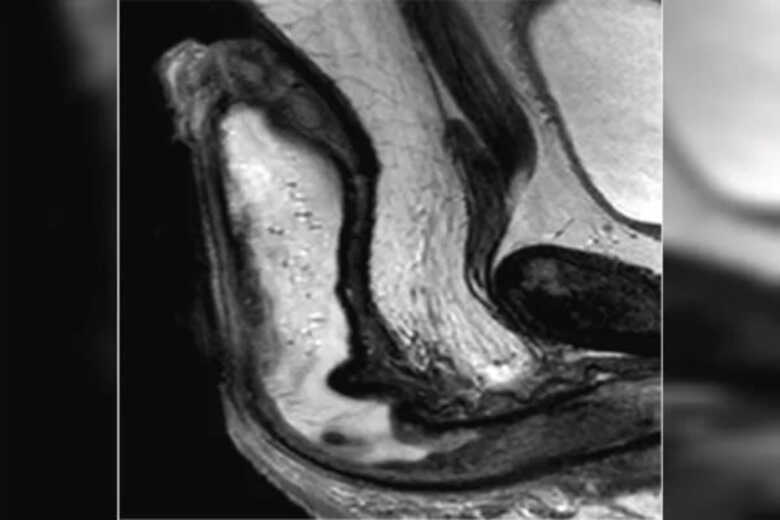

Ressonância magnética revelou que o órgão genital do brasileiro estava preenchido de lÃquido (Foto: Reprodução/Urology Cases Report)